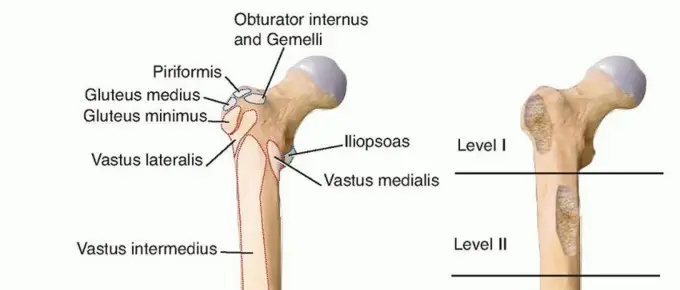

التحضير الجيد قبل الجراحة هو مفتاح لنجاح عملية استبدال مفصل الورك. يشمل ذلك تقييماً دقيقاً للمريض باستخدام الفحص السريري والتصوير، بالإضافة إلى التخطيط الجراحي لاختيار أفضل خيارات التثبيت.

الفحص والتصوير قبل الجراحة

يعد الفحص الدقيق والتصوير الشامل ضرورياً لتقييم تشريح الورك وتخطيط الجراحة.

**الأشعة السينية (Anteroposterior pelvic radiograph):** يتم تصور التشريح الحقي بشكل أفضل على الأشعة السينية الأمامية الخلفية للحوض. تُظهر هذه الأشعة تفاصيل مهمة مثل:

- **الورك المصاب بالتهاب المفاصل:** كما يظهر في الشكل 1A، حيث نرى وركاً مصاباً بالتهاب المفاصل لدى رجل يبلغ من العمر 74 عاماً مع وجود أجهزة سابقة في رأس الفخذ.

- **مخطط الدمعة والسطح المفصلي الحقي:** يوضح الشكل 1B مخطط الدمعة والسطح المفصلي الحقي.

- **تحديد درجة التسطيح الجانبي لرأس الفخذ:** يوضح الشكل 2 مقدار التسطيح الجانبي لرأس الفخذ من قاع التجويف الحقي. يشير السهم الأيسر إلى الحدود الجانبية للدمعة، والتي تمثل القاع التشريحي للتجويف الحقي، بينما يمثل السهم الأيمن القاعدة الجانبية للتجويف الحقي المصاب بالتهاب المفاصل. هذا التقييم يساعد الجراح في تحديد مدى إعادة تشكيل التجويف الحقي المطلوب.